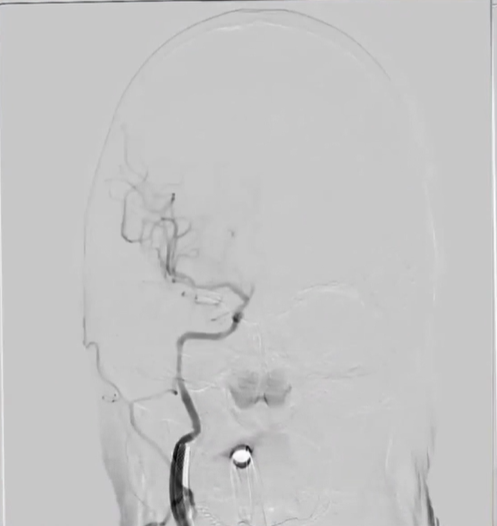

左侧椎动脉起始部成形

病历夹什么径技·第152期|串联营病历夹:川陕大营_https://www.jmylbn.com_新闻资讯_第21张

病历夹什么径技·第152期|串联营病历夹:川陕大营_https://www.jmylbn.com_新闻资讯_第22张

<<滑动查看下一张图片>>

确认血栓远近端

病历夹什么径技·第152期|串联营病历夹:川陕大营_https://www.jmylbn.com_新闻资讯_第23张

血管再通后造影

病历夹什么径技·第152期|串联营病历夹:川陕大营_https://www.jmylbn.com_新闻资讯_第24张

血管再通及左椎支架植入

病历夹什么径技·第152期|串联营病历夹:川陕大营_https://www.jmylbn.com_新闻资讯_第25张

病历夹什么径技·第152期|串联营病历夹:川陕大营_https://www.jmylbn.com_新闻资讯_第26张

病历夹什么径技·第152期|串联营病历夹:川陕大营_https://www.jmylbn.com_新闻资讯_第27张

左椎支架植入后造影

病历夹什么径技·第152期|串联营病历夹:川陕大营_https://www.jmylbn.com_新闻资讯_第28张